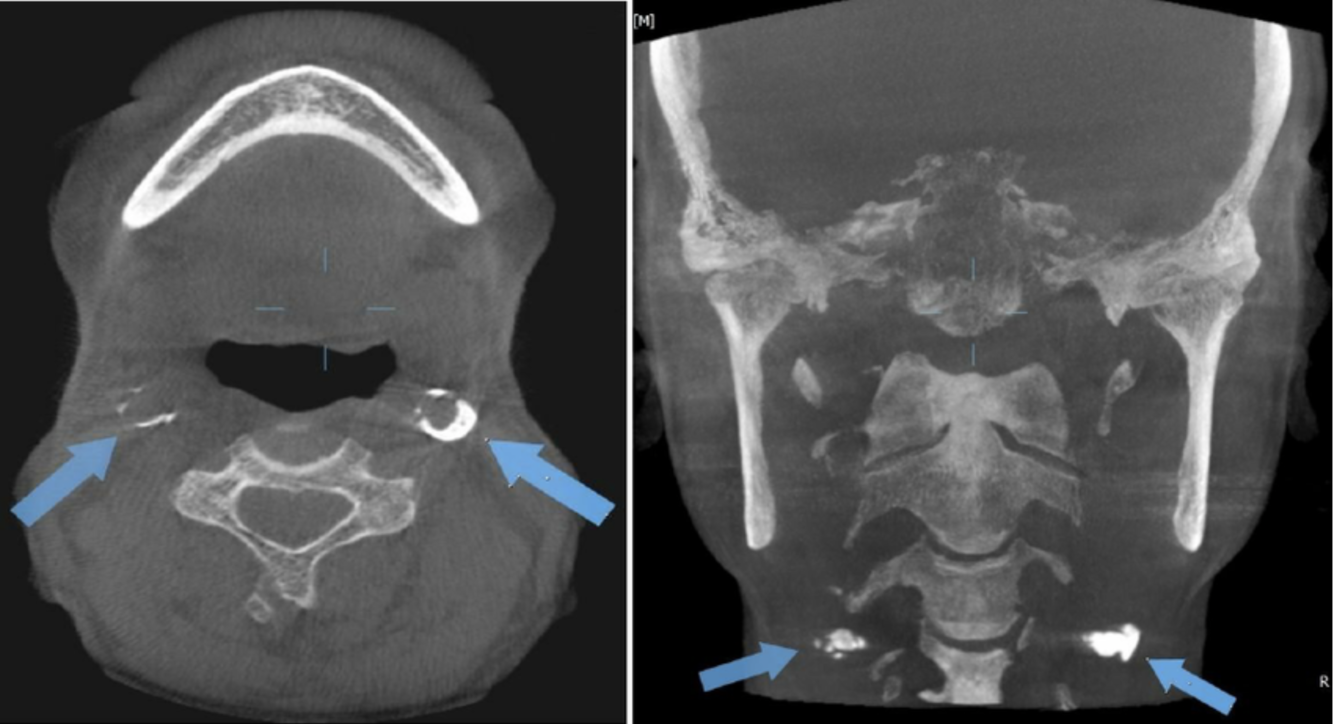

8

Q

What view?

A

Axial

9

Coronal